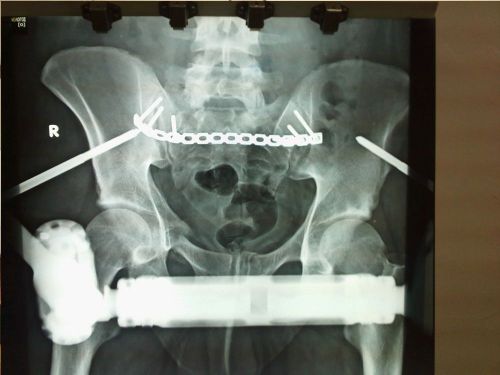

- 3 weeks post operation. Posterior part of pelvis fixed with open reduction internal fixation and anterior part of pelvis fixed with external fixation (Medical Team for the Management of Pelvic and Acetabulum Fractures in 401 General Military Hospital of Athens-Greece)